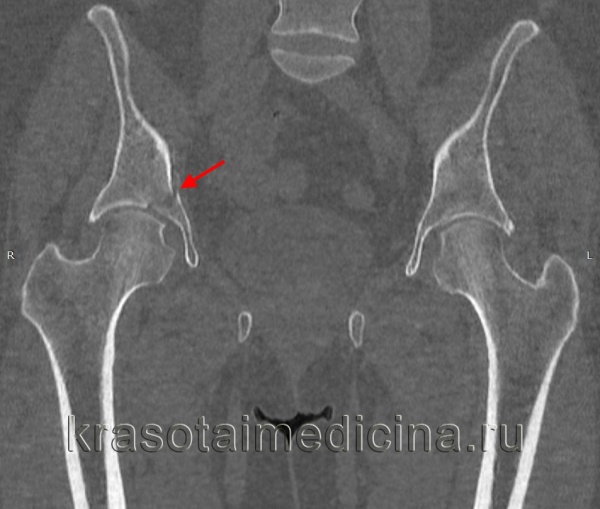

Для уточнения диагноза выполняют обзорную рентгенографию таза и рентгенографию поврежденного сустава в трех дополнительных проекциях. По возможности пациента направляют на КТ таза, поскольку эта методика позволяет более точно оценить тяжесть травмы и характер смещения отломков. Диагностическая ценность компьютерной томографии возрастает при повреждениях задней колонны и оскольчатых переломах.

Для определения типа перелома, оценки степени смещения, решения вопроса о необходимости оперативного лечения и выбора соответствующего доступа необходимо провести рентгенологическое исследование таза в косых проекциях и КТ. Существуют разные хирургические доступы к вертлужной впадине. Среди них доступ по Kocher-Langenbeck, подвздошно-паховый доступ, расширенный подвздошно-бедренный, модифицированный подвздошно-бедренный, по Stoppa, трехлучевой доступ, комбинированный переднезадний и чрескожный доступы.